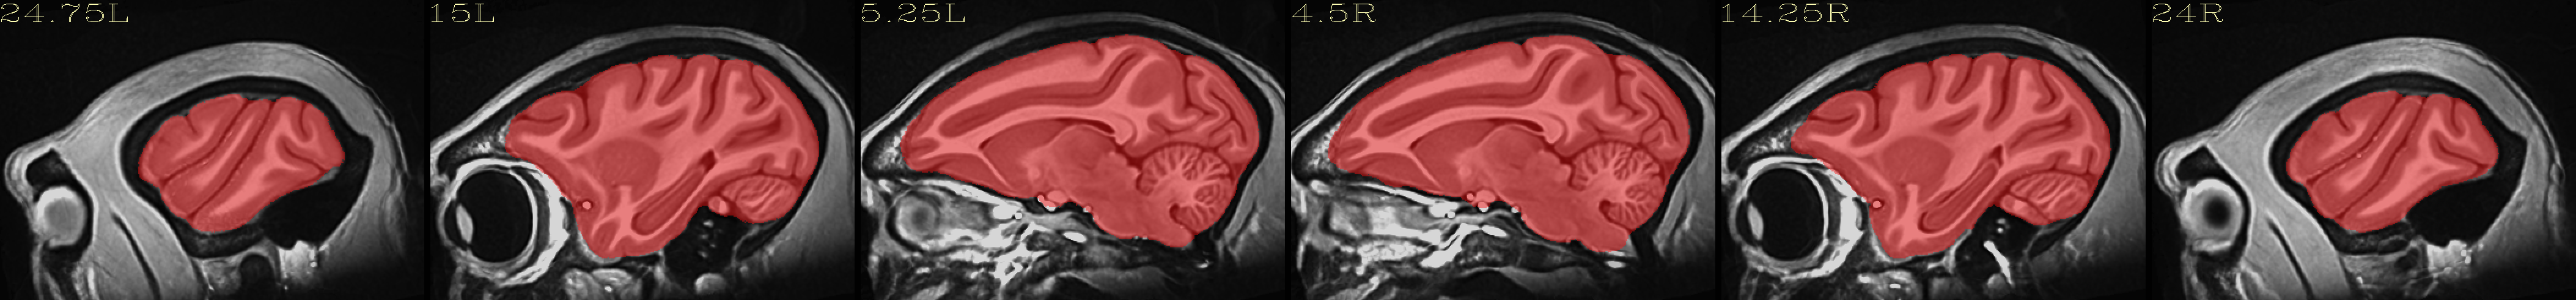

Skull-stripped NMT with 4-tissue segmentation |

|---|

|

Skull-stripped NMT with D99 atlas |

The script used to make these images with ``@chauffeur_afni`` is

here: do_view_nmt_v1.3.tcsh